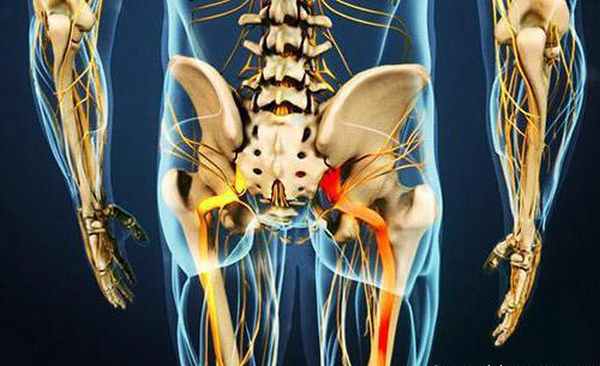

Иннервация

К надкостнице медиальных поверхностей ветвей седалищных костей и нижних ветвей лобковых костей у мужчин прикрепляются ножки полового члена (лат. crus penis ) образованные пещеристыми телами его корня (лат. radix penis ). К седалищному бугру прикрепляются следующие мышцы мочеполовой области [en] промежности: глубокая поперечная мышца промежности [en] (лат. m. transversus perinei profundus ), поверхностная поперечная мышца промежности [en] (лат. m. transversus perinei superficialis , может быть не у всех людей), седалищно-пещеристая мышца [en] (лат. m. ischiocavernosus ), а к седалищной ости — седалищно-копчиковая мышца [de] (лат. m. ischiococcygeus ) диафрагмы таза [3] .

![Седалищный нерв болит: что делать? Причины, симптомы и терапия при ишиасе]()

Седалищный нерв болит – что делать? Принципы лечения ишиаса будут подробно рассмотрены ниже. Также вы узнаете о том, почему возникает это заболевание и каковы его симптомы.